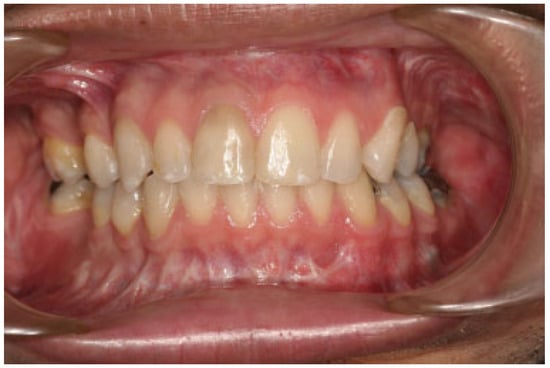

:Case Report